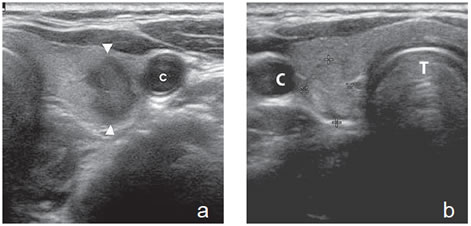

En nódulos coloideos de mayor tamaño, sobre 20 mm- 25 mm, el contenido suele ser mixto, predominando el componente líquido, con espacios quísticos de tamaño variable y asimétricos, separados por finos septos que corresponden a bandas de tejido tiroideo (Figura 20a), que le dan típicamente un aspecto multiloculado, o áreas quísticas entremezcladas con elementos sólidos de tejido hiperplástico y tejido granulatorio reactivo, de distinto espesor y forma, con imágenes pseudo nodulares o vegetantes, de ecogenicidad similar al parénquima tiroideo, que protruyen hacia los espacios quísticos (Figura 2b). Las áreas sólidas generalmente aparecen hipervascularizadas al “doppler color” (Figura 20b y c), pero a medida que aumenta el tamaño del nódulo la vascularización va disminuyendo.

Figura 20. a) Nódulo coloideo de forma redondeada, con múltiples

tabiques finos de aspecto multiloculado. Adosado a uno de

los tabiques se observa un foco hiperecogénico que corresponde a

coloide espeso (flecha); b) y c) Nódulo coloideo, mixto, que muestra

que las áreas sólidas aparecen hiperevascularizadas. C: carótida

común izquierda.